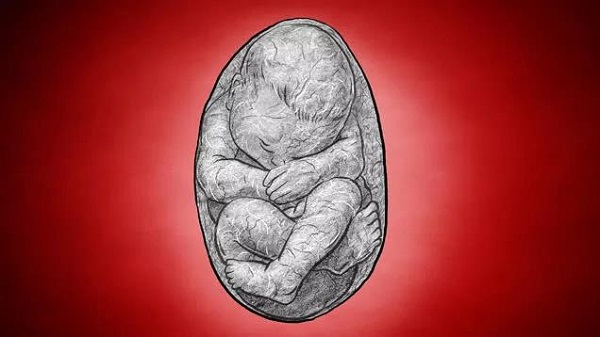

外科医生纪录的桑斯怪胎

石胎

石胎(lithopedion,stone babies), 一种非常罕见的妊娠,是腹腔妊娠的一种结局,而腹腔妊娠属于异位妊娠,发生率为 0.0054%,石胎占其中的 1.3%~2%。腹腔妊娠时,胚胎多在 3 月后死亡,胎儿软组织自动溶解,骨骼难以被吸收,形成钙盐沉着,即形成石胎。